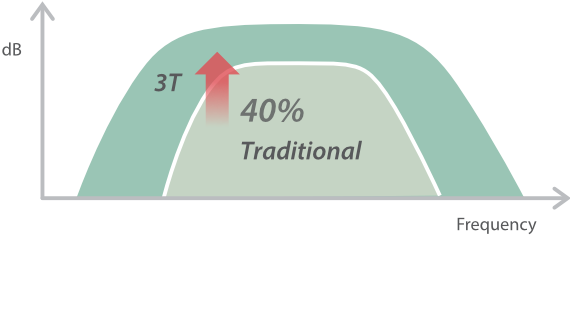

Mindray stellt mit seinen bahnbrechenden Ultraschallsystemen unter Beweis, worauf es im klinischen Alltag ankommt. Wir entwickeln kontinuierlich innovative Ultraschalltechnologien. Das DC-60 ECHO mit X-Insight ist ein exzellenter Beweis daf├╝r, wie unsere Ger?te h?chsten Anspr├╝chen gerecht werden und die moderne Medizintechnik noch besser und effizienter machen. Voller Vertrauen blicken wir mit X-Insight in die Zukunft. Das DC-60 Expert ├╝berzeugt als extrem leistungsf?hige Ultraschalll?sung. Mit diesem System leistet Mindray einen weiteren Beitrag dazu, in der Ultraschallbildgebung neue Ma?st?be zu setzen.